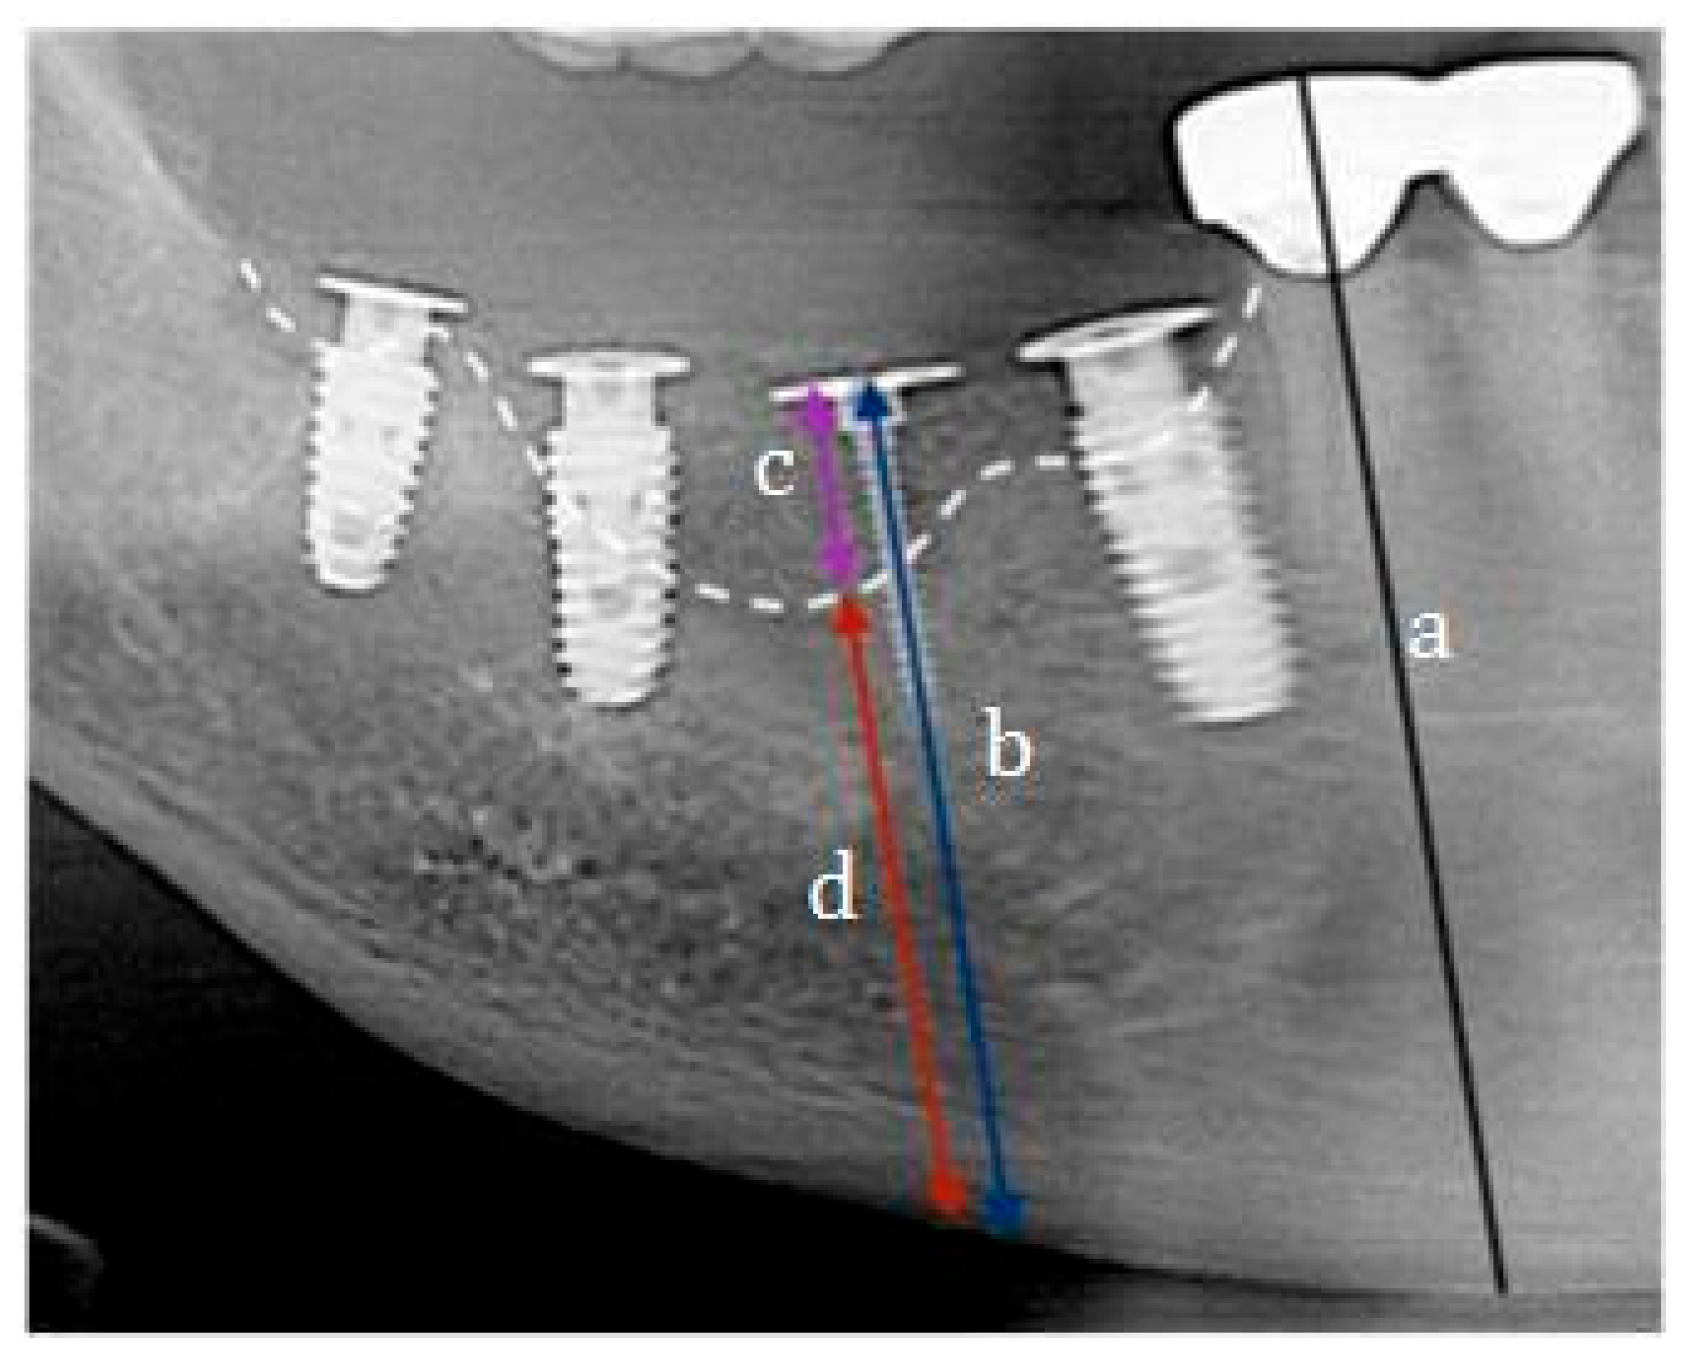

- Sohn, D.S. Reconstruction of three-dimensional alveolar ridge defects utilizing screws and implant abutments for the tent-pole grafting techniques. In Essential Techniques of Alveolar Bone Augmentation in Implant Dentistry, 2nd ed.; Tolstunov, L., Ed.; Wiley Blackwell: Hoboken, NJ, USA, 2023; pp. 404–418. [Google Scholar]

- Sohn, D.S.; Lui, A.; Choi, H. Utilization of tenting pole abutments for the reconstruction of severely resorbed alveolar bone: Technical considerations and case series reports. J. Clin. Med. 2024, 13, 1156. [Google Scholar] [CrossRef]